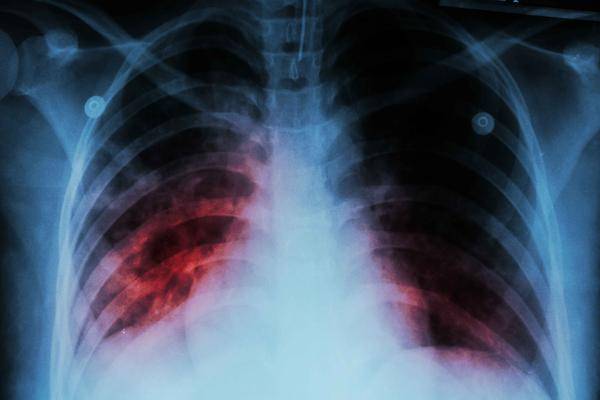

可是受到各種因素的影響,近些年來肺髒疾病的發病率越來越高,尤其是肺癌,現已成為我國惡性腫瘤中發病率第一,死亡率第一的惡性腫瘤。

另外,臨床上多數患者在確診肺癌時,病情已經發展至了中晚期,這種情況下治療的難度增加了很多,所以才出現了死亡率升高的問題。

因此我們才要做好定期體檢的操作,才能更為清楚直觀的了解肺髒的健康程度,一旦發現有異常,及時干預,進而達到防止癌細胞肆虐的效果。